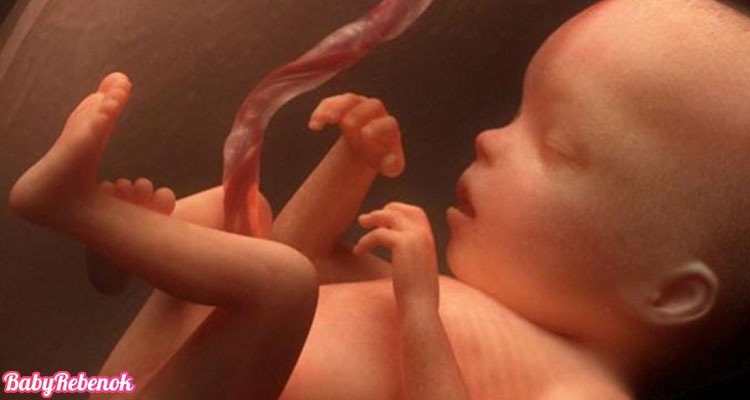

Плод уже похож на полностью сформированного ребенка, только он намного меньше новорожденного малыша. Уже практически завершилось формирование мозга и жировой ткани. Его личико приобрело правильные черты, ручки и ножки окрепли, бровки стали гуще, на глазах появились реснички, а на голове первый пушок. Носик ребенка пока еще похож на маленькую кнопочку, потому что не полностью сформировалась спинка носа.

Сейчас у ребенка активно формируются потовые железы и рецепторы, отвечающие за тактильные ощущения. Он пытается все пощупать руками, трогает свое лицо, стенки матки, с удовольствием сосет пальчик.

Примечательно, что рост головного мозга слегка замедляется, а вот развитие тактильных ощущений плода сильно развивается. Так, например, сейчас будущий малыш уже активно все трогает вокруг себя, свое тело, сосет пальчики, играется с пуповиной и даже пытается толкаться в ответ на прикосновение к животу.

Волосы на голове растут с высокой интенсивностью, увеличивается выразительность бровей, но так как меланин ребенка находится на низком уровне – цвет волос неярко выражен. Головной мозг ребенка развился до такой степени, что он уже сам совершает то или иное движение и проверяет, может ли он шевелить пальцами на руках. Он начинает трогать свое тело, плаценту и изучать внутренний мир с помощью прикосновений. Из-за высокой интенсивности движений вы будете чувствовать своего ребенка еще лучше, чем раньше.

У малыша на 22 неделе замедляется рост мозга. Происходит созревание его определенных структур, отвечающих за тактильные ощущения – плод изучает себя и все окружающее на ощупь, активно сосет пальчик. Устанавливаются нервные связи, созревают уже сформировавшиеся нейроны головного мозга. Активно включаются в работу потовые железы.

Вот так выглядит Ваш малыш на 22 неделе